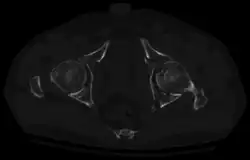

Axial CT image (viewed on bone windows) of a complex comminuted left acetabular fracture involving both anterior and posterior columns. -

In all cases, CT scan can assist in identifying impacted bone pieces, which may be found within the joint, and MRI may be done to identify the extent of potential injury to the sciatic nerve.